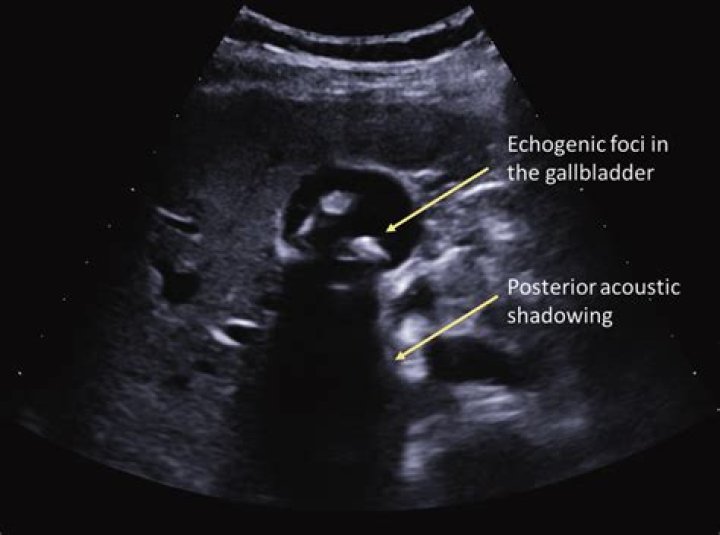

Gallstones on ultrasound have the appearance of hyperechoic structures within the gallbladder with distal acoustic shadowing. Sludge in gallbladder may also be seen, with an appearance of hyperechoic layering within the gallbladder. Sludge, unlike stones, does not cast acoustic shadowing.

Gallstones appear as echogenic foci in the gallbladder. They move freely with positional changes and cast an acoustic shadow. (See the image below.) Cholecystitis with small stones in the gallbladder neck.

What are shadowing gallstones?